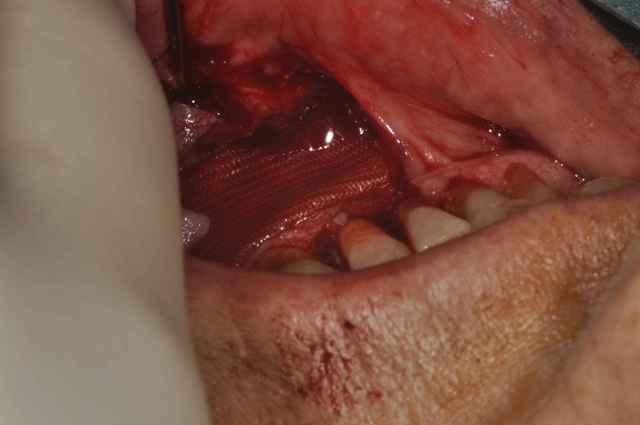

Petit cas qui permet de sortir de l'ordinaire.

Exérése d'un Kyste d'origine dentaire aprés avoir repris les endo sur 32/33/34.

Comblement avec du B-TCP et membrane vicryl.

sur la première photo on voit un tricot de vicryl ou bien, compresse pour faire marsupialisation ?

- acte fait sous anesthésie locale sans problème.

- pour le V3, j'avais fait un scanner,la corticale était refoulé et le kyste était sans contact direct avec le canal.